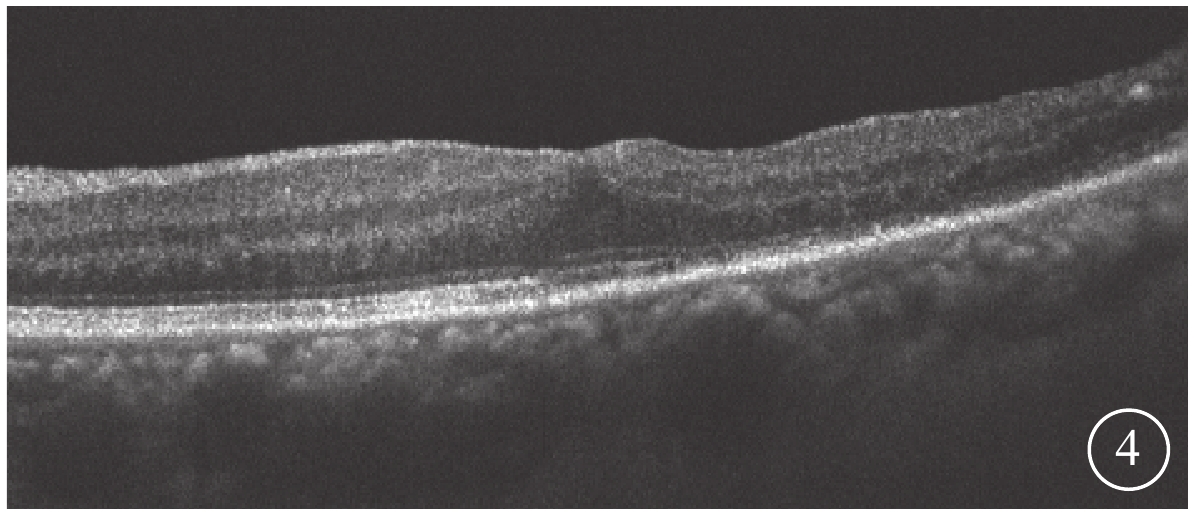

末次隨訪時,患眼BCVA為0.15~0.6,平均BCVA為0.42±0.24。患眼后房型人工晶狀體位正,黃斑部出血吸收。FFA檢查發現,患眼顳下視網膜動脈分支處強熒光點消失(圖3)。OCT檢查發現,患眼黃斑結構逐漸恢復(圖4)。所有患眼均未發生視網膜脫離、黃斑裂孔等并發癥。

圖4

圖1同眼手術后OCT像。黃斑中心凹形態恢復

圖4

圖1同眼手術后OCT像。黃斑中心凹形態恢復

末次隨訪時,患眼BCVA為0.15~0.6,平均BCVA為0.42±0.24。患眼后房型人工晶狀體位正,黃斑部出血吸收。FFA檢查發現,患眼顳下視網膜動脈分支處強熒光點消失(圖3)。OCT檢查發現,患眼黃斑結構逐漸恢復(圖4)。所有患眼均未發生視網膜脫離、黃斑裂孔等并發癥。

圖4

圖1同眼手術后OCT像。黃斑中心凹形態恢復

圖4

圖1同眼手術后OCT像。黃斑中心凹形態恢復